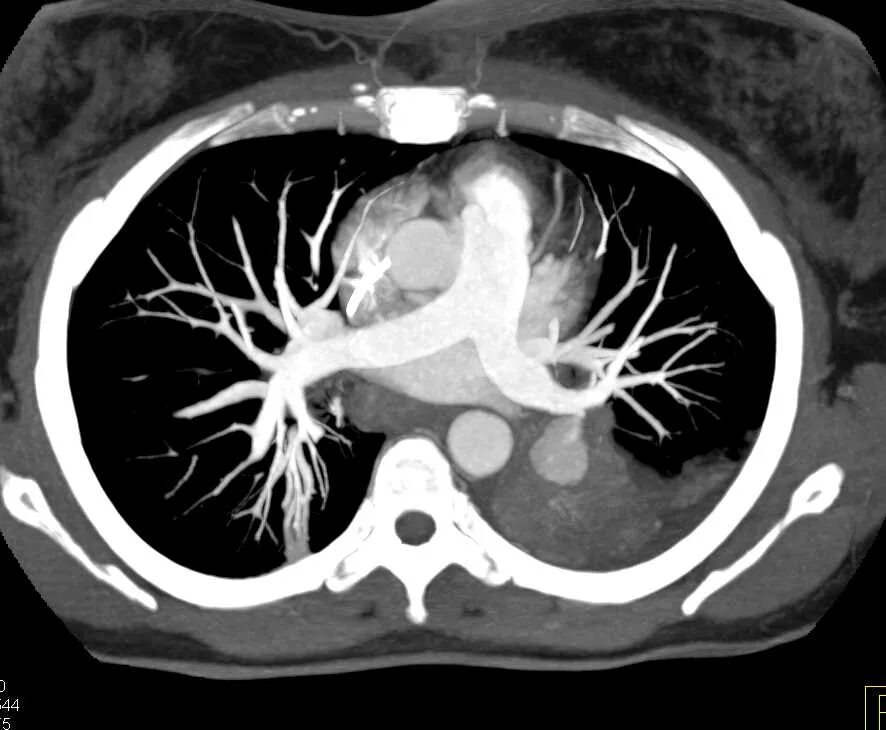

Легочный ствол на кт